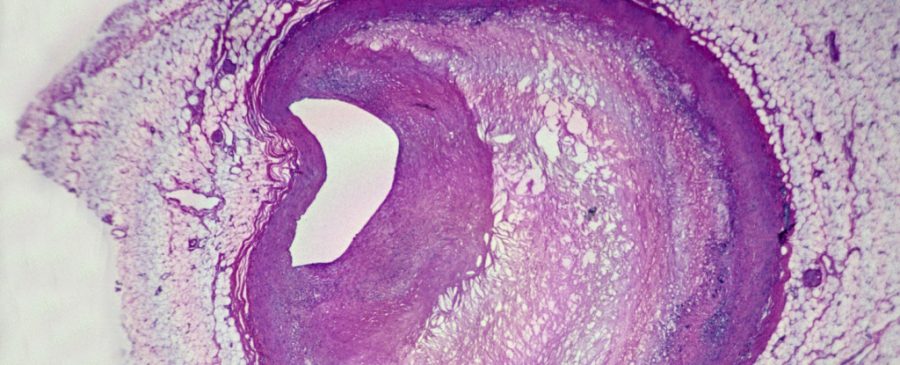

میکروپلاستیکها همچنین زیر میکروسکوپهای قدرتمند قابل مشاهده بودند: محققان قطعات پلاستیکی با لبههای ناصاف را در سلولهای ایمنی به نام ماکروفاژها و داخل پلاکهای چربی مشاهده کردند. بررسی نمونههای بافتی نشان داد که بیمارانی که پلاستیک در پلاکهایشان داشتند، سطح بالاتری از نشانههای التهابی نیز داشتند.

ذرات پلاستیکی با لبههای ناصاف درون ماکروفاژها و رسوبات چربی شریانهای مسدود مشاهده شد.